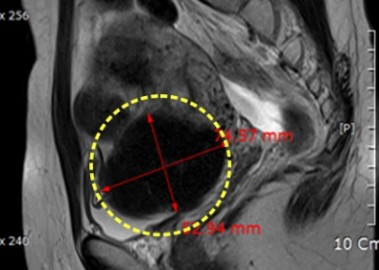

자궁근종 6cm 치료 전후